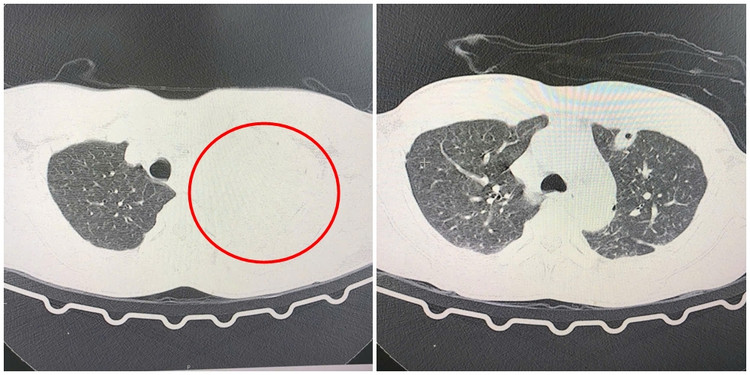

| Hình ảnh CLVT phổi trái mờ toàn bộ do chảy máu đã hồi phục tốt sau phẫu thuật. |

Kết quả chụp CLVT lồng ngực chẩn đoán bệnh nhân bị tràn dịch, tràn khí màng phổi trái, có biểu hiện mất máu cấp. Nhận định đây là một ca cấp cứu tối khẩn, diễn biến phức tạp, các bác sĩ nhanh chóng chuyển bệnh nhân tới phòng mổ cấp cứu.

Dưới sự hỗ trợ của hệ thống nội soi hiện đại, phẫu thuật viên đưa dụng cụ nội soi vào khoang màng phổi kiểm tra có khoảng 800g máu cục và phát hiện kén khí ở đỉnh phổi bị vỡ gây tràn khí, máu chảy ra từ dây chằng đỉnh phổi trái do đứt dây chằng.

Kíp mổ khéo léo cầm máu điểm chảy, cắt và khâu kén khí vỡ, đồng thời rửa sạch khoang màng phổi và đặt dẫn lưu. Sau 1 giờ phẫu thuật với tổng 2 lít máu truyền hồi sức, ca mổ thành công.